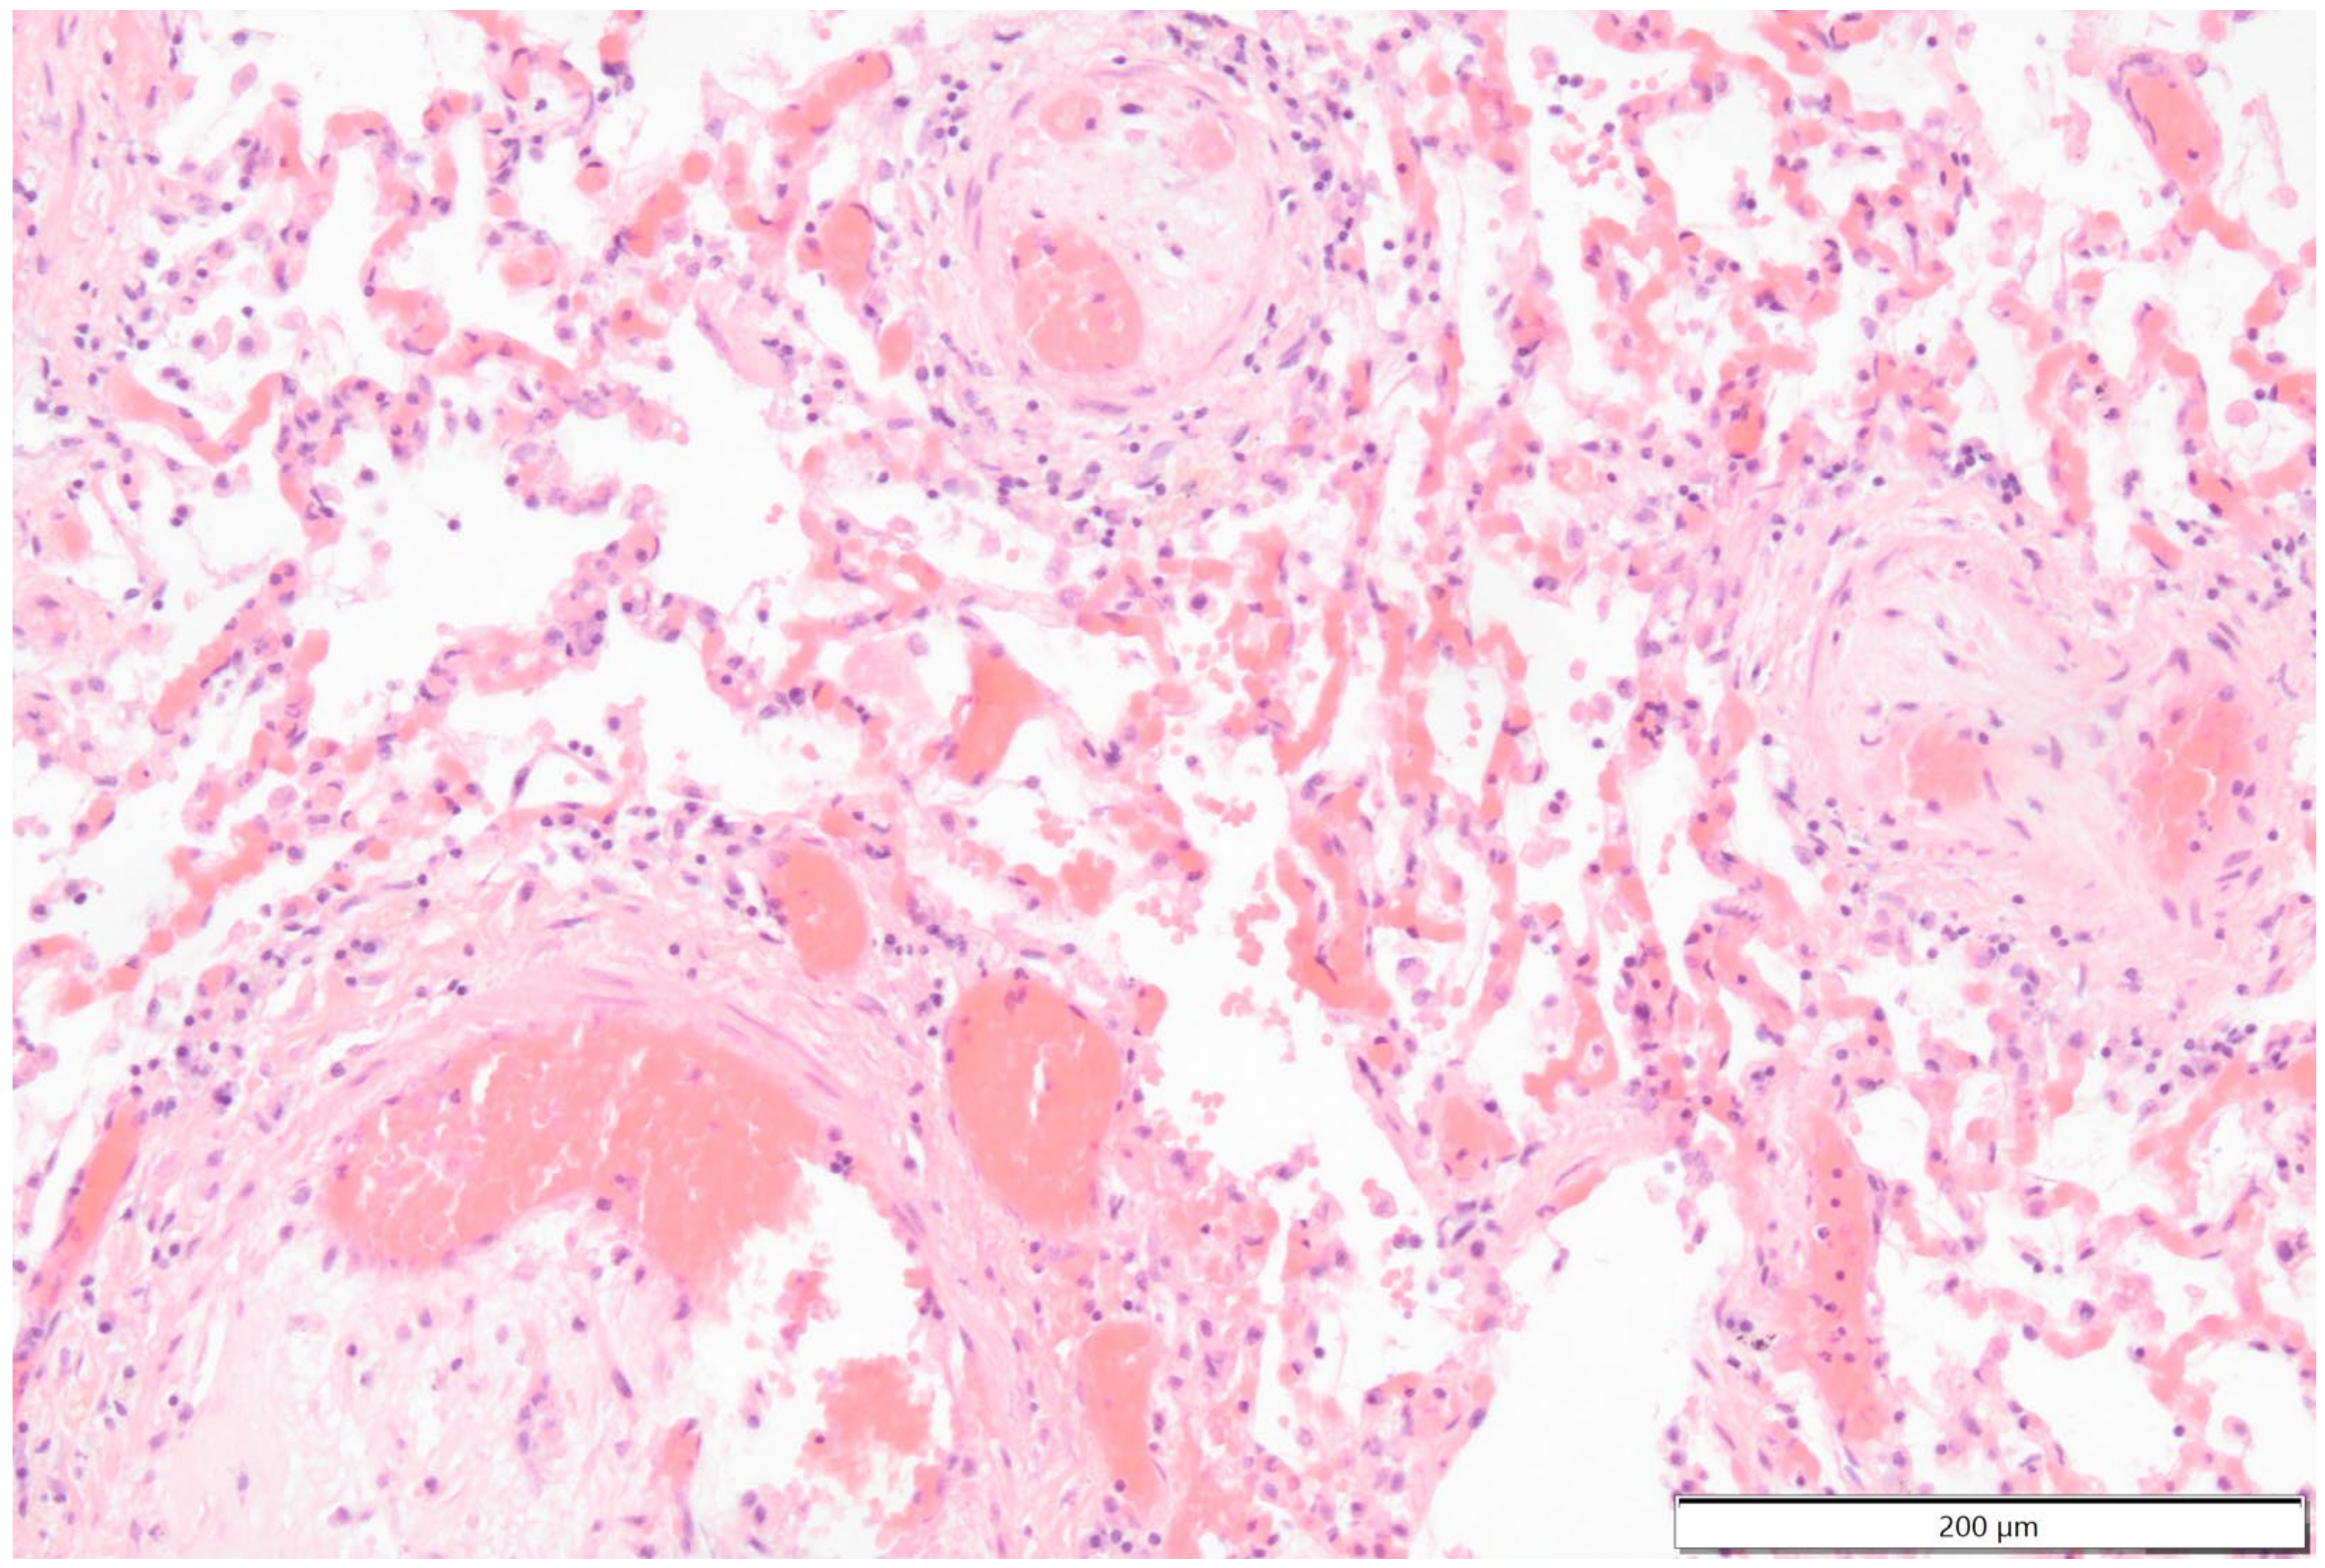

Histologically the right ventricular thrombus was characterized by a massive central zone of amorphous eosinophilic material with occasional scattered cellular debris (fibrin and necrosis) and scattered deposits of hemosiderin and hematoidin pigments. Peripherally, the thrombus consisted of a variably thick layer of connective tissue that was infiltrated by moderate numbers of macrophages, lymphocytes and plasma cells. This inflammatory infiltrate extended into the adjacent myocardium. At the site of electrode insertion, the myocardium was focally replaced by connective tissue and adipose tissue. Multiple coronary vessels had thickened walls that partially occluded the lumens. Multiple pulmonary vessels were obstructed by similar material as described in the right ventricle (thromboemboli) and here this was interspersed with small irregular vascular channels (recanalization) (Figure 9, Figure 10, Figure 11 and Figure 12). Histopathological analysis confirmed marked chronic mural endocarditis and myocarditis with chronic thrombus formation in the right ventricle and pulmonary arteries.

Figure 11.

Photomicrographs of the thromboembolus in the pulmonary artery: 2× and 10× magnification images show the periphery with attachment to the endothelium, mild edema of the vascular wall, small-caliber blood-filled channels (recanalization) interspersed between areas of connective tissue, fibrin and inflammatory cells.

Figure 12.

Photomicrograph shows that the lumen of smaller pulmonary arteries is partially occluded by thromboembolic material. Hematoxylin & Eosin staining 40× magnification.